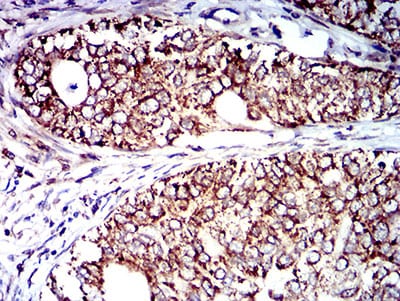

| IHC | 1/200 - 1/1000 | Human,Mouse,Rat |

CD129. also known as interleukin-9 receptor (IL-9R), is a cell surface protein belonging to the type I cytokine receptor family. It consists of a ligand-specific α-chain (IL-9Rα) that pairs with the common γ-chain (γc, CD132) to form a functional receptor complex. IL-9R is primarily expressed on immune cells, including mast cells, T helper (Th2) cells, regulatory T cells (Tregs), B cells, and epithelial cells. It binds interleukin-9 (IL-9), a pleiotropic cytokine involved in allergic inflammation, immune regulation, and tumorigenesis. Signaling through IL-9R activates JAK-STAT (Janus kinase-signal transducer and activator of transcription), MAPK, and PI3K pathways, promoting cell survival, proliferation, and cytokine production.

CD129 antibodies are essential tools for studying IL-9/IL-9R signaling in diseases like asthma, atopic dermatitis, and certain cancers (e.g., Hodgkin’s lymphoma, lung adenocarcinoma). They enable detection of IL-9R expression via flow cytometry, immunohistochemistry, or Western blot, aiding in identifying IL-9-responsive cell populations. Therapeutic CD129-targeting agents, including neutralizing antibodies, are under exploration to block pathogenic IL-9 signaling in allergic disorders or enhance anti-tumor immunity. However, IL-9’s dual role in both promoting inflammation and maintaining tissue repair complicates therapeutic targeting. Research using CD129 antibodies continues to clarify IL-9R’s context-dependent functions, informing potential clinical applications.